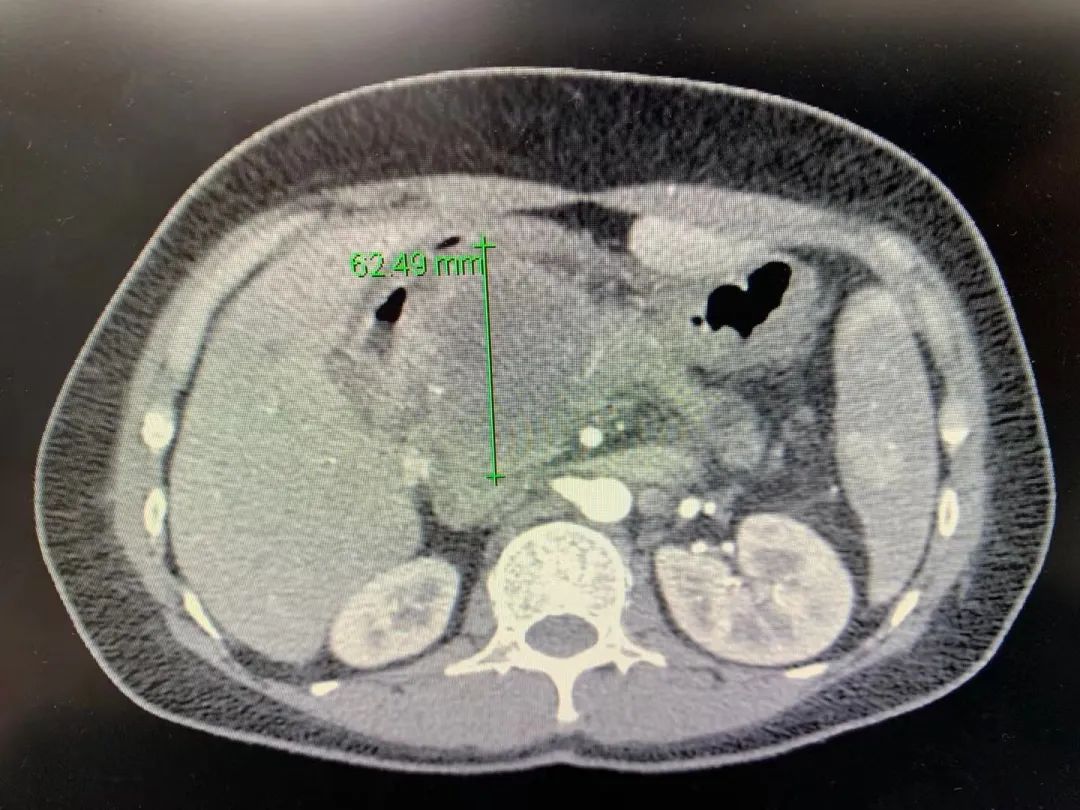

为了明确包块的性质,秦女士和家人来到新桥医院肝胆外科,经过超声内镜穿刺活检病理诊断为“胰腺癌”,位于胰头位置的肿瘤足有直径62mm大,已经与腹主动脉分支、肝总动脉紧紧地长在一起,并且肠系膜上动脉周围淋巴结已有转移,门静脉、肠系膜上静脉也被肿瘤360°包饶。查血肿瘤标志物Ca199:101.8 U/mL,超过正常值3倍。

▲化疗前CT肿瘤情况